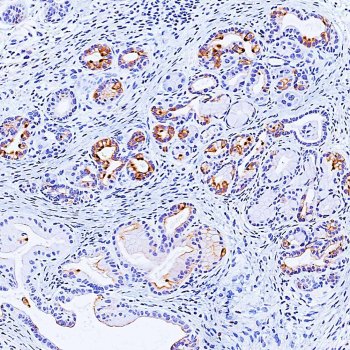

A transdiferenciação de células acinares pancreáticas para um fenótipo ductal (acinar-a-ductalmetaplasia, ADM) ocorre após lesão ou inflamação do pâncreas e é um processo reversível. No entanto, na presença de mutações de ativação Kras ou sinalização persistente do EGFR, células que foram submetidas à ADM podem progredir para neoplasia intraepitelial pancreática (PanINs), e eventualmente, câncer de pâncreas. Em modelos animais transgênicos, a ADM e PanINs são iniciadas por ligações de afinidade elevada para EGFR ou ativação de mutações Kras, mas os mecanismos de sinalização subjacentes não eram bem compreendidos.

Agora, os pesquisadores mostraram que a proteína cinase D1 (PKD1) é suficiente para acionar o processo de reprogramação para um fenótipo ductal e desencadear a progressão para PanINs.

Para testar o efeito da PKD1, os pesquisadores usaram um modelo 3-D de células pancreáticas derivadas de cobaias. Eles manipularam a expressão de PKD1, bloqueando o gene ou induzindo sua atividade. Cerca de uma semana depois de estimular a expressão PKD1, os pesquisadores puderam ver que as células acinares se transformaram em células ductais. O bloqueio do PKD1 levou à diminuição da formação de células ductais e à diminuição das lesões.